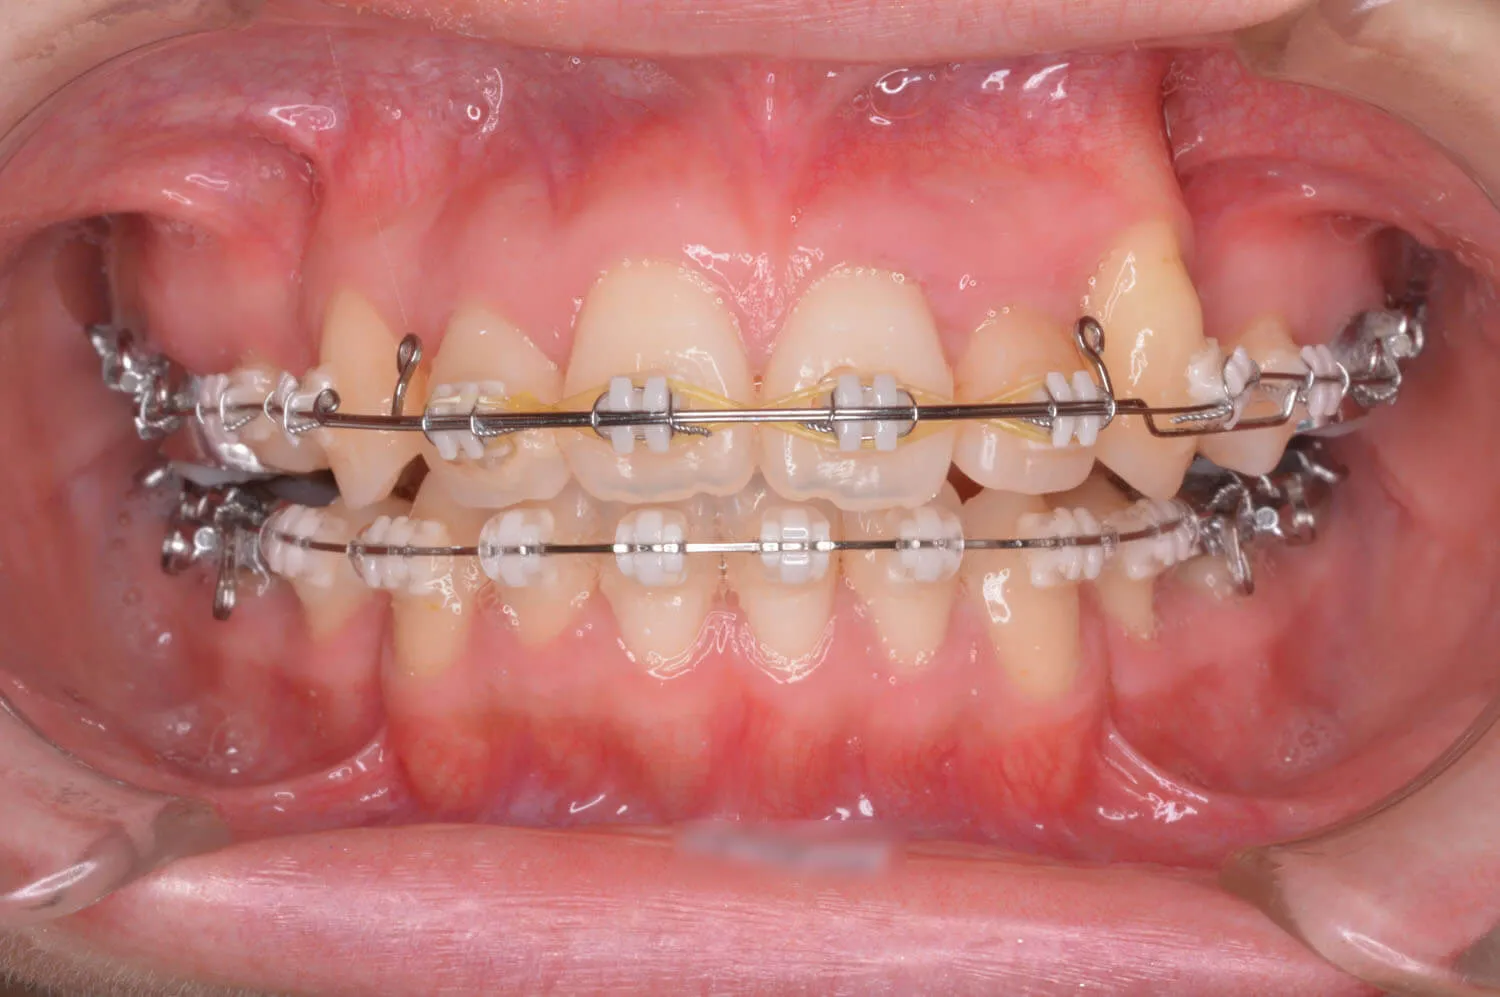

ブラケット装置が装着されました。

犬歯のけん引をはじめました。